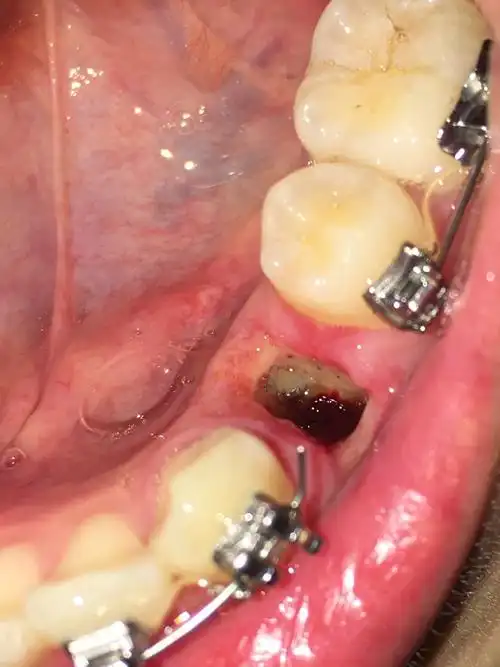

有图慎点反复干槽症四号牙有没有懂的朋友进来解答一下呀